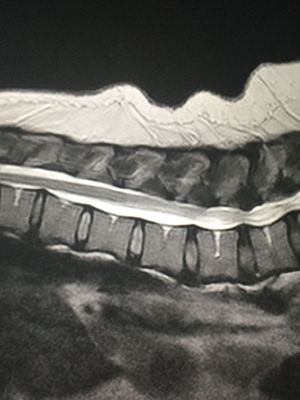

What do you see in this MRI ?

Best explanation gets a cookie.

Spinal cord compression in T12-L1 by slipped disk And maybe a spinal cord compression in L4-L5?

Correct. Patent also has signs of spinal stenosis.

Protrusion and disc buldging